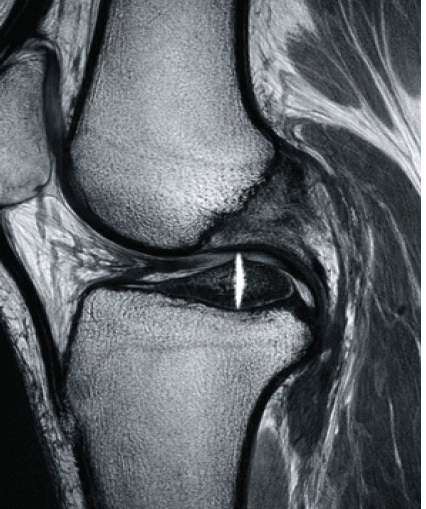

Single-Stage Management of Anterior Cruciate Ligament Tear with Dual Menisci Bony Root Avulsion: A Rare Case Report and Review of Literature

Mukesh Garg , Vishesh Verma

………………………………p.283-289